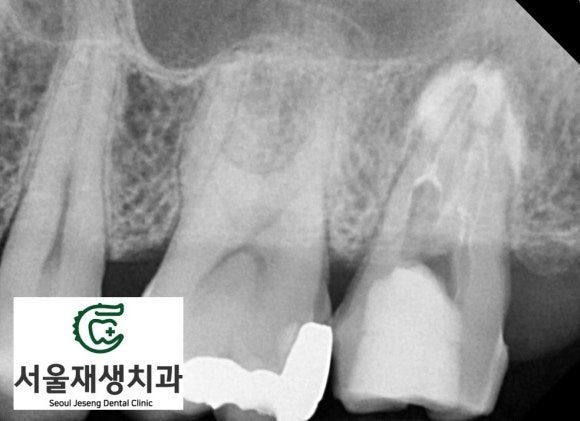

CT와 일반 엑스레이를 통한 추적 관찰, 그리고 점차 나아지는 경과

재신경치료는 단기간에 끝나는 치료가 아니기에, 치료 과정을 꾸준히 모니터링하는 것이 중요합니다.

저희 서울재생치과에서는 신경치료용 CT와 구내 엑스레이를 주기적으로 촬영하여 염증의 축소 과정을 추적 관찰합니다.

환자분의 경우에도 정기적인 검사를 통해 염증이 점차 줄어들고 상악동의 상태가 호전되는 것을 확인할 수 있었습니다.

치아의 흔들림이 사라지고, 식사 시 환자분의 불편감도 크게 감소했습니다.

엑스레이 상으로도 치아 주위의 염증이 감소한 것으로 보입니다.

확실한 진단을 위해 CT를 촬영해보았습니다.

치료 전 촬영한 CT입니다.

상악동을 가득 메우고 있는 회색의 액체상이 관찰됩니다.

치료 4개월 차에 촬영한 사진입니다.

세면대에서 물이 빠지듯이, 상악동 내를 가득채우고 있는 염증물질이 축소된 것을 확인할 수 있습니다.

치료를 종료하기로 했습니다.

나머지는 시간에 맡기면 됩니다.